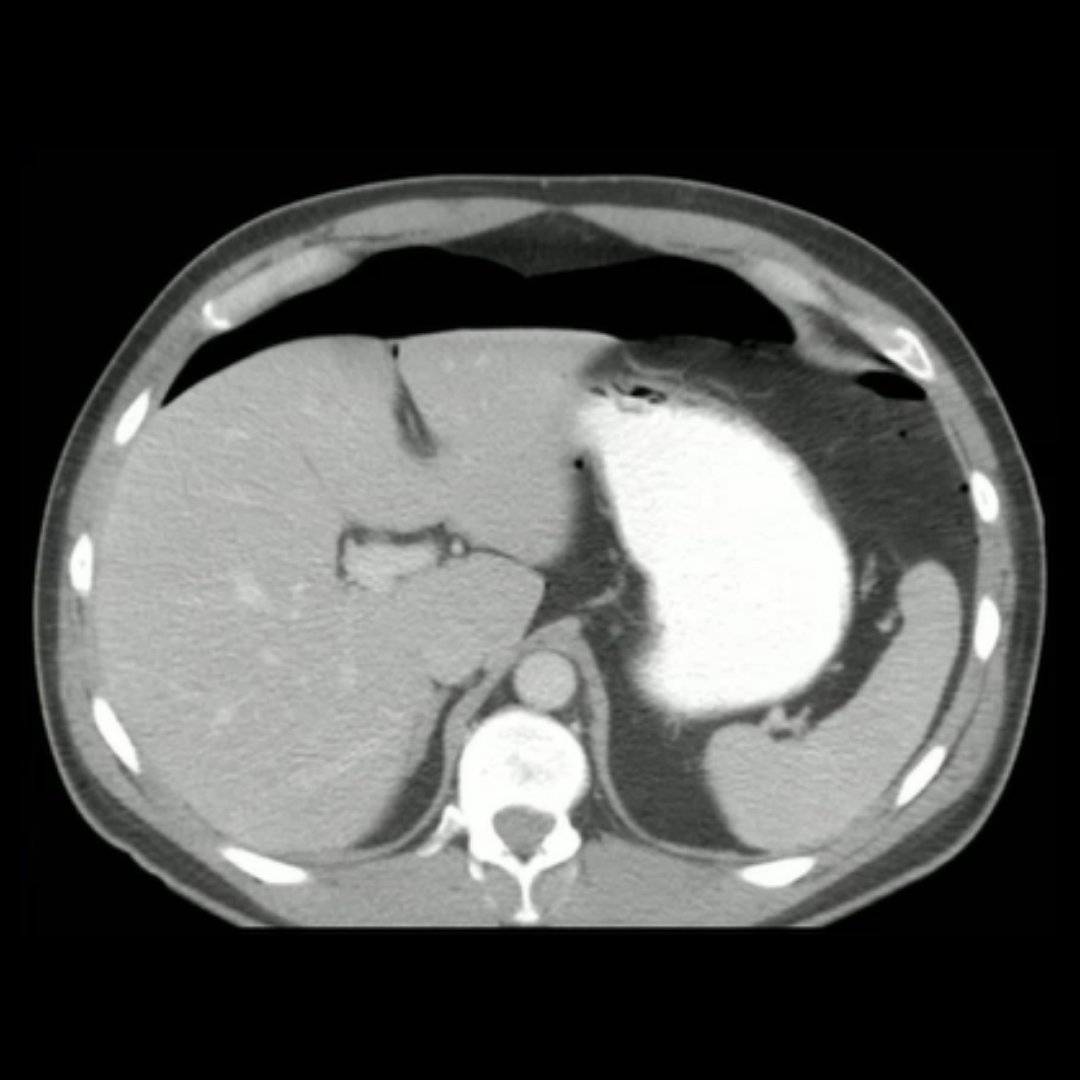

New CME: Complications of Bariatric Surgery

Presented by Vincent Mellnick, MD